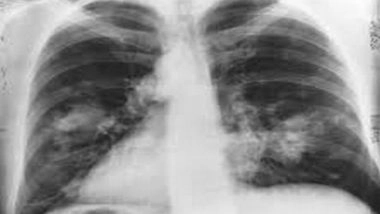

Combining the test with analysis of clinical risk factors, a protein biomarker, and followed by computed tomography imaging, DELFI helped detect 94 per cent of patients with cancer across stages and subtypes. This included 91 per cent of patients with earlier or less invasive stage I/II cancers and 96 per cent of patients with more advanced stage III/IV cancers.

Lung cancer is the most common cause of cancer death, claiming almost 2 million lives worldwide each year. However, fewer than 6 per cent of Americans at risk for lung cancers undergo recommended low-dose computed tomography screening, despite projections that tens of thousands of deaths could be avoided, and even fewer are screened worldwide, explains senior study author Victor E. Velculescu, M.D., PhD, professor of oncology and co-director of the Cancer Genetics and Epigenetics Program at the Johns Hopkins Kimmel Cancer Center.

The DELFI approach found that patients who were later determined to have cancer had wide variation in their fragmentome profiles, while patients found not to have cancer had consistent fragmentome profiles. Subsequently, researchers validated the DELFI technology using a different population of 385 individuals without cancer and 46 individuals with cancer. Overall, the approach detected over 90 per cent of patients with lung cancer, including those with early and advanced stages, and with different subtypes.